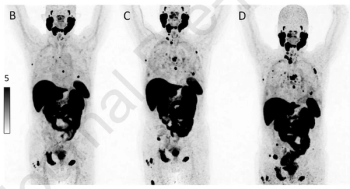

For patients with biochemical recurrence of prostate cancer, PSMA PET imaging may facilitate a 12.8 percent lower incidence of prostate cancer mortality in contrast to the combination of CT and bone scan, according to long-term outcome estimates from a new decision-analytic modeling study.

Earlier detection of PSMA-avid lesions in post-radiotherapy patients with increases in PSA levels < 2 ng/ml above nadir were reportedly associated with a significantly lower incidence of distant metastases and lower overall mortality rates.